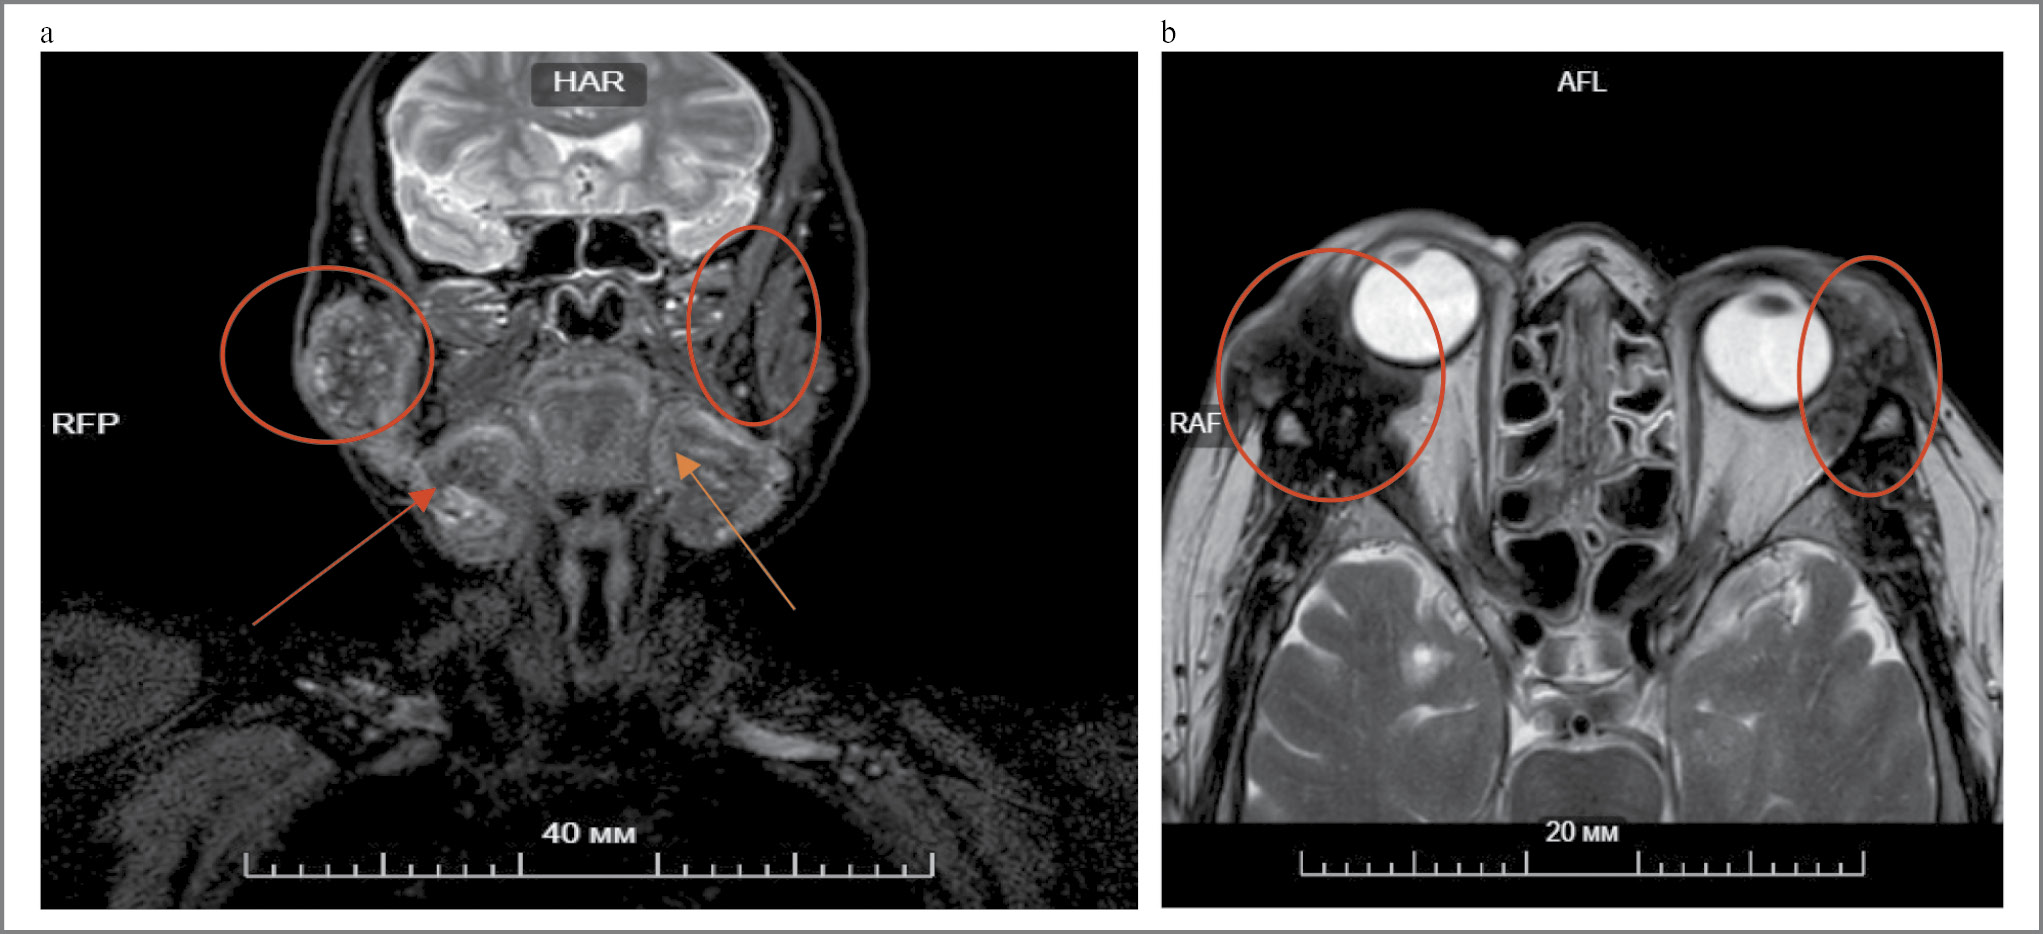

На МР-томографии мягких тканей лица и орбит выявлено увеличение околоушных слюнных желез: правой – до 62×45×48 мм, левой – до 47×35×60 мм, а также подчелюстных слюнных желез – до 43×32×55 и 47×35×60 мм соответственно. Наружная прямая мышца правого глаза утолщена до 5 мм, инфильтрирована по наружному контуру и компримирована объемным образованием, располагающимся в верхнем наружном квадранте орбиты, размерами 51×35×32 мм, без четких границ, с распространением в подкожно-жировую клетчатку и на область слезной железы. В проекции слезной железы левой орбиты визуализированы патологические массы размерами 35×21×28 мм (рис. 5).

Рис. 5. МР-томография мягких тканей лица и орбит: a – увеличенные в размерах поднижнечелюстные и околоушные слюнные железы; b – правая орбита (объемное образование в верхнем наружном квадранте орбиты без четких границ, с распространением в подкожно-жировую клетчатку и на область слезной железы); левая орбита (в проекции слезной железы патологические массы с неоднородным МР-сигналом).

Fig. 5. Magnetic resonance imaging of the soft tissues of the face and orbits: a – enlarged submandibular and parotid salivary glands; b – right orbit (volumetric mass in the upper outer quadrant of the orbit without clear boundaries, with spreading into the subcutaneous fatty tissue and to the lacrimal gland area); left orbit (pathologic masses with inhomogeneous MR-signal in the projection of the lacrimal gland).